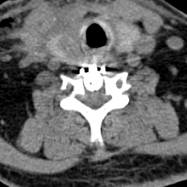

术后CT显示骨赘已彻底切除